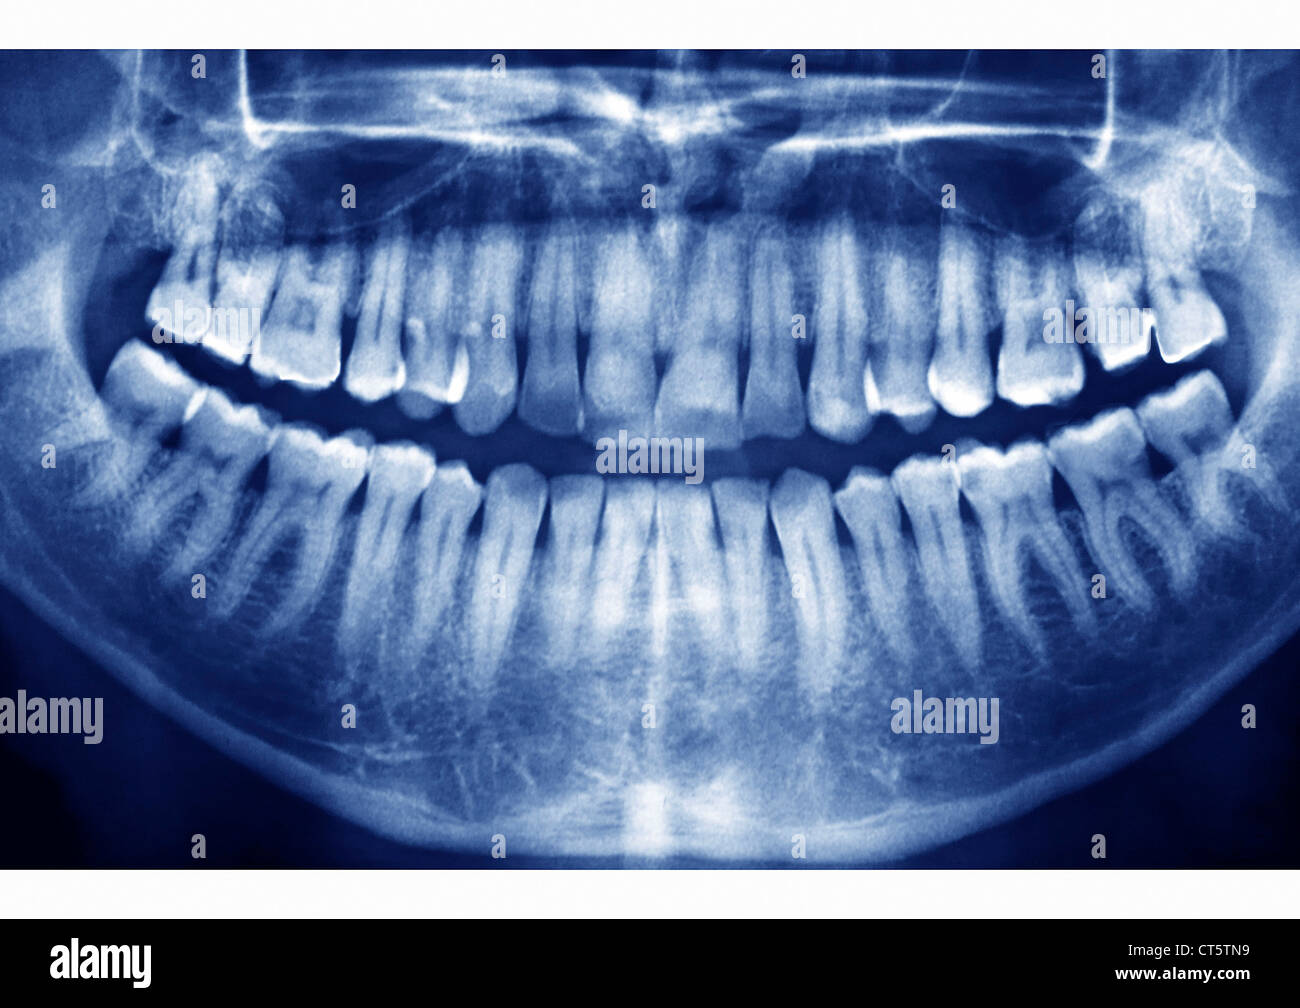

Panorex dental. This image is exceptionally useful in diagnosing a wide range of issues. The image is either displayed digitally on a computer or. Without this critical piece of data we can sometimes miss pathologic lesion such as tumors or cysts extra teeth and a whole host of other conditions that need surgical treatment in a timely fashion.

Now a standard part of the imaging protocols at many practices digital panoramic x-rays provide a large amount of diagnostic information and great efficiency. OPG otherwise known as panorex or orthopantomogram is a full mouth panoramic scan dental x-ray of the lower and upper jaws. Our Technology June 20 2018 by Reedley Dental 0.

Diagnostic images of a patients complete dentition are produced almost instantly with a digital panoramic imaging system and the newest systems provide. It is commonly performed by dentists and oral surgeons in everyday practice and. Tracy Robinson is a well-trained Veneta Dentist call us today. Dental Digital Panoramic X-ray. Without this critical piece of data we can sometimes miss pathologic lesion such as tumors or cysts extra teeth and a whole host of other conditions that need surgical treatment in a timely fashion. Initially the patient will sit in a chair with their chin on a small ledge. Now a standard part of the imaging protocols at many practices digital panoramic x-rays provide a large amount of diagnostic information and great efficiency. Your dental hygienist doesnt have to constantly come in and out of the room to change film saving you time. During the panorex X-ray the patient is asked to bite down on a special tool that assists the operator in positioning the patients head in the correct position.

A panorex is imaging machinery that is capable of providing a full view of the upper and lower jaws teeth temporomandibular joints and sinuses. Dimensions of Dental Hygiene is a monthly peer-reviewed journal that reconnects practicing dental hygienists with the nations leading educators and researchers. Access Dental providing professional dental care. It is commonly performed by dentists and oral surgeons in everyday practice and. Here you can discover how panoramic radiography works. This image is exceptionally useful in diagnosing a wide range of issues. Welcome to the new age of dental x-ray technology.